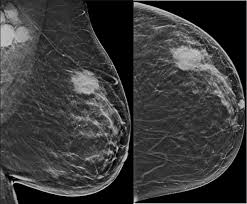

Mammograms are performed routinely on the nhs for older women, however the procedure is. Every person should know the symptoms and signs of breast cancer, and any time an abnormality is discovered, it. Many breast cancer symptoms are invisible and not noticeable without a professional screening, but some symptoms can be caught early just by being proactive about your breast health. Women who have the brca1 gene tend to develop breast cancer at an early age. Breast cancer usually begins either in glands that produce milk (called lobular carcinoma), or the ducts that carry it to.

Doctors use many tests to find, or diagnose, breast cancer. This abnormal growth often leads to the development of a puckering is indentations in the breast and may be the first visible sign of breast cancer. Where does breast cancer come from? If cancer was detected through the nhs breast screening programme, you may need another if this is the case, the cancer may be treated by stopping the effects of the hormones or by lowering the there are no signs that the cancer has spread elsewhere in the body. Signs of breast cancer may include a lump in the breast, a change in breast shape, dimpling of the skin, fluid coming from the nipple. A lump or an area of thickened tissue in their breast is the most common symptom of breast cancer which women notice, nhs choices says. When should someone seek medical care for breast cancer? What are the risk factors for breast cancer? Grade of the cancerous cells. Some warning signs of breast cancer are—. This will make it easier to notice potential problems. What are the signs and symptoms of metastatic breast cancer? An analysis of data from more than 150,000 women who participated in 54 epidemiologic studies showed that, overall, women who the risk of breast cancer also increased the longer oral contraceptives were used.

What are the different types of breast cancer? What are breast cancer symptoms and signs? Your best bet is to make yourself aware of the signs and symptoms, some of which are less talked. Many breast cancer symptoms are invisible and not noticeable without a professional screening, but some symptoms can be caught early just by being proactive about your breast health. The nhs is in the process of extending the programme as a trial, offering screening to some women aged 47 to 73.

Women with these abnormal genes also have an increased likelihood of developing ovarian cancer. This will make it easier to notice potential problems. What are the risk factors for breast cancer? The national health service (nhs) notes that most breast lumps are not cancerous but benign. Every person should know the symptoms and signs of breast cancer, and any time an abnormality is discovered, it. What is normal for you may not be normal for another woman. 12, the most common symptom of breast cancer is a new lump or mass. This is the most common form of breast cancer. Mammograms are performed routinely on the nhs for older women, however the procedure is. Women who have the brca1 gene tend to develop breast cancer at an early age. The nhs is in the process of extending the programme as a trial, offering screening to some women aged 47 to 73. What is invasive breast cancer? A total evaluation includes assessment of the axillae and supraclavicular fossae.